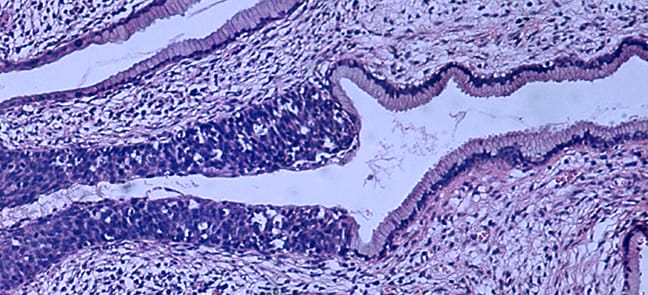

Researchers studied genetic information from tumors from more than 100 patients from Norway and Mexico. Rangel-Escareño’s expertise in the statistical and computational analysis of genetic data—or computational genomics—played an important role in the study. The amount of information from DNA is staggering. Billions of nucleotides—the building blocks of DNA—must be analyzed to map a single genome, the full set of genetic instructions needed to make cells, tissue, and organs in the human body.